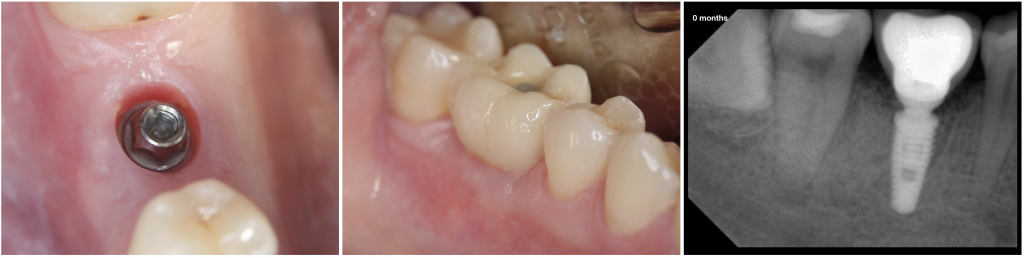

Fig. 2- Healing after 2 months, the definitive restoration was delivered.

During the observation period (12 months), the four implants were osseointegrated, and functional, mechanical or biological complications were not reported. The volume of the soft tissues and the horizontal ridge were lower than in the initial situation. However, the radiographic controls showed bone over the implant platform.